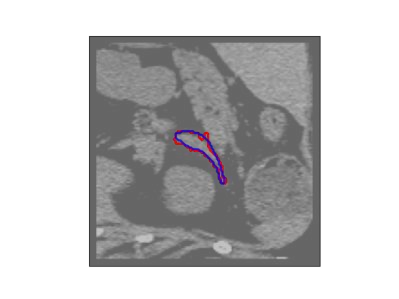

The human annotations are imperfect, especially when produced by junior practitioners. Multi-expert consensus is usually regarded as golden standard, while this annotation protocol is too expensive to implement in many real-world projects. In this study, we propose a method to refine human annotation, named Neural Annotation Refinement (NeAR). It is based on a learnable implicit function, which decodes a latent vector into represented shape. By integrating the appearance as an input of implicit functions, the appearance-aware NeAR fixes the annotation artefacts. Our method is demonstrated on the application of adrenal gland analysis. We first show that the NeAR can repair distorted golden standards on a public adrenal gland segmentation dataset. Besides, we develop a new Adrenal gLand ANalysis (ALAN) dataset with the proposed NeAR, where each case consists of a 3D shape of adrenal gland and its diagnosis label (normal vs. abnormal) assigned by experts. We show that models trained on the shapes repaired by the NeAR can diagnose adrenal glands better than the original ones. The ALAN dataset will be open-source, with 1,594 shapes for adrenal gland diagnosis, which serves as a new benchmark for medical shape analysis. Code and dataset are available at https://github.com/M3DV/NeAR.